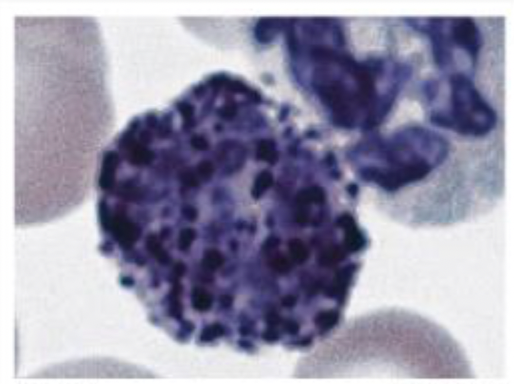

Monocyte